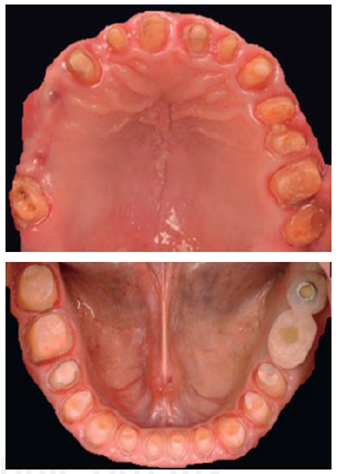

Este reporte documenta el tratamiento de un paciente masculino de 68 años de edad. Comenta tener dificultades masticatorias y digestivas debido a importante desgaste dental, se dice incómodo al sonreír; no refirió padecimientos sistémicos, fumó durante ocho años, diagnosticado con hipertensión arterial controlada. Se observa atrición generalizada, ausencia de dientes 14, 15, 16, 46 y periodonto sano (Figuras 1a4). Los dientes 13 y 37 presentaban tratamiento de conductos y periápice sano, sin restauración (Figura 5).

Para cuantificar la reducción de DVO, se examinó el perfil facial y la estética mediante análisis fotográfico y vídeo (Figuras 6y7). Además de realizar un cuidadoso análisis del montaje de los modelos diagnósticos en articulador semiajustable (Figura 8). También se examinó el esquema oclusal (presentaba relación borde a borde) y la estructura dental con la que se contaba (Figura 3). La revisión dinámica fue clave para determinar que el paciente exhibe una línea de sonrisa alta (Figura 9).

Un nuevo plano oclusal se estableció preparando el arco superior e inferior para coronas completas (Figura 24).

Se adaptaron restauraciones de polimetilmetacrilato termocurable, para el segmento anterosuperior se solicitó al laboratorio dental la colocación de dientes de tablilla para conseguir un efecto más agradable visualmente. La cementación de las mismas se realizó con cemento a base de óxido de zinc y eugenol reforzado con polímeros IRM®, Densply, a cuya mezcla se le añadió Maxitrol® por sus propiedades antibióticas, así como antiinfl amatorias (Figuras 25a28).

Se optó por disilicato de litio como sistema restaurador definitivo (coronas IPS e.max™ monolíticas, maquilladas en sector posterior y estratificadas en anterior). El medio cementante seleccionado fue RelyX Ultimate™ (Figuras 33a36).